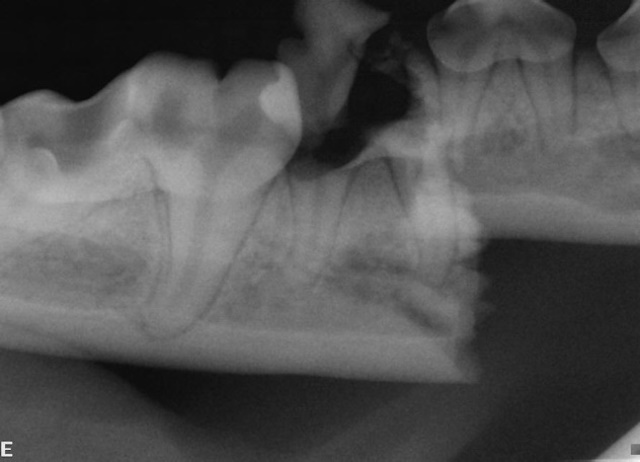

Mandibular fracture is stabilized first with interdental wire and a circumferential wire (image above). Initial intraoral radiograph showing a displaced mandibular body fracture (image below).